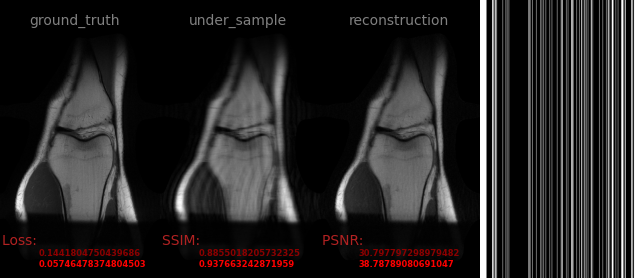

AVS-Net

Image-to-Image

medical

avs_b20